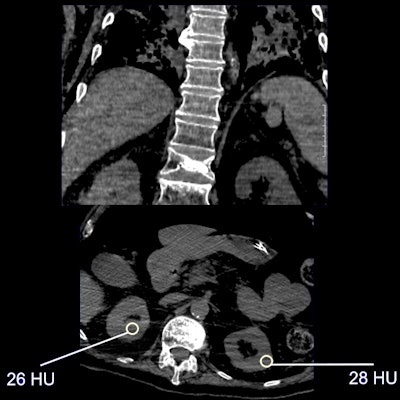

Imaging features of renal complications due to COVID-19 include renal parenchyma attenuation, perinephric fat stranding, and renal infarction (which can lead to vascular coagulopathy), presenter Prof. Riccardo Manfredi of the Gemelli University Hospital in Rome told session attendees. Manfredi also listed possible renal sequelae due to COVID-19, such as electrolyte dysfunction, acute kidney injury, and renal replacement therapy.

"Although imaging findings [of renal complications due to COVID-19] may not be specific, renal parenchyma attenuation and perinephric fat stranding can be detected on chest CT," he said. "And correlation [between imaging and] laboratory results can be a predictor of acute kidney injury."

- Keep the kidneys in mind when reading chest CT exams, since the organ is often visible on caudal images. Look for perinephric fat stranding and renal density on unenhanced CT studies.